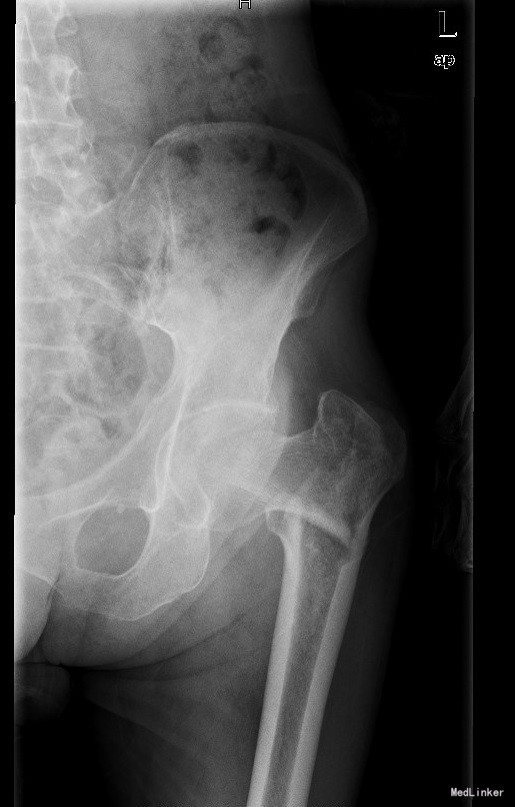

查体:T:36.5oC,P:80次/分,R:20次/分,BP:134/70mmHg。神志清楚,无病容,皮肤巩膜无黄染,全身浅表淋巴结未见肿大。颈静脉正常。心界正常,心律齐,各瓣膜区未闻及杂音。胸廓未见异常,双肺叩诊呈清音,双肺呼吸音清,未闻及干湿啰音及胸膜摩擦音。腹部外形正常,全腹柔软,无压痛及反跳痛,腹部未触及包块,肝脏肋下未触及,脾脏肋下未触及,双肾未触及。双下肢无水肿。 专科检查:跛行步态,双手多指指间关节稍屈曲尺偏畸形,左肘关节屈曲畸形。左肘关节及左髋部压痛,左侧肘关节屈曲10°畸形,双腕关节屈10°伸10°左右,活动受限。左髋关节屈伸活动受限,左下肢较右下肢短缩约4.0cm。颈干角85°左右,纵向叩击痛明显Allis征(+)、踝关节活动轻度受限 辅助检查:左股骨转子间陈旧性骨折

诊断:1、左股骨转子间陈旧性骨折畸形愈合伴髋内翻畸形;2、类风湿性关节炎累及多关节 治疗:全麻下行左股骨转子间陈旧性骨折截骨矫形取髂骨及异体骨植骨、PFNA内固定术